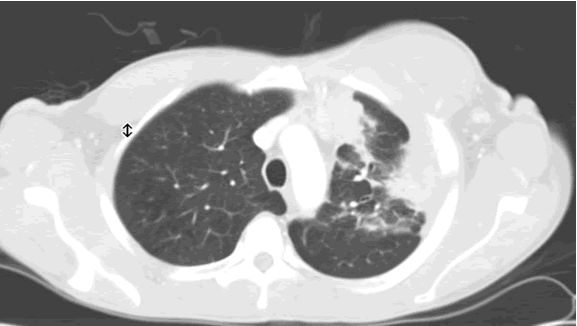

PA and lateral chest film revealed patchy consolidation of the left lung with a large pleural-based mass, left apical pleural thickening, and right upper lobe scarring (Figure 1). Helical CT scan of the chest, abdomen, and pelvis with contrast demonstrates a large, 10.8 x 4.1 cm left pleural-based mass extending into the chest wall and left breast (Figure 2). There was periosteal thickening and irregularity of adjacent ribs. Multiple enlarged mediastinal, left hilar, and supraclavicular nodes were noted, the largest 1.5 x 2.6 cm in the AP window or station five region. There was patchy consolidation of the left and right upper lobes. An MRI of the thorax with contrast was obtained and confirmed the presence of left supraclavicular adenopathy and an enhancing mass with extension into the chest wall involving the ribs, infiltration of the pectoralis muscle, and extension into the left lung parenchyma. The main differential diagnoses at this time were neoplasm (sarcoma, advanced lung cancer, mesothelioma, lymphoma, osteosarcoma).

A Tru-cut needle biopsy was performed at bedside which revealed nonspecific pathologic findings, but a repeat with increased sampling revealed acute and chronic inflammation with granulation tissue containing Actinomyces confirmed by periodic acid shift (PAS), Gomori’s methamine silver (GMS), and modified Gram stains (Figure 3). Treatment began with intravenous Penicillin G (4 million units every 4 hours for a 6 week course) which will be followed by oral amoxicillin for 6-12 months. A repeat CT scan was planned in 4 weeks, as actinomycosis is known to colonize malignant tissue. The patient, at three month follow up, was doing well from a pulmonary standpoint and had regression of his chest wall mass.